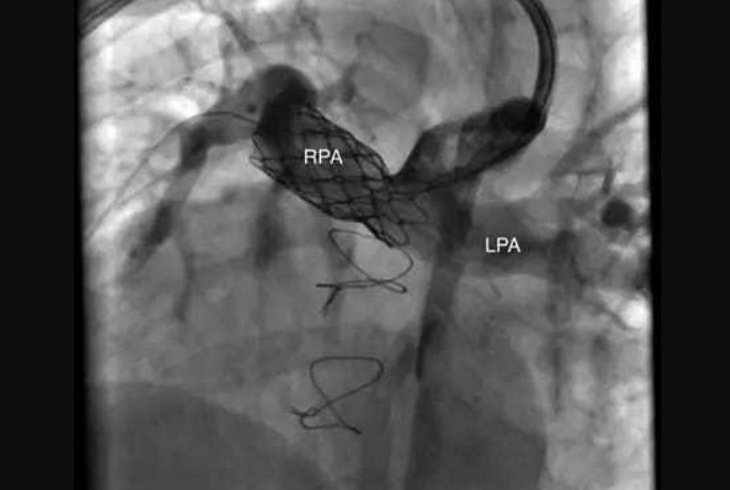

Stent placement is a catheter-based procedure where a small mesh tube (stent) is inserted into a narrowed artery or vessel. The stent helps keep the vessel open, ensuring smooth blood flow to the heart or other areas of the body.

Stent placement is performed under local anesthesia or mild sedation. A catheter is inserted through a blood vessel, usually in the leg, and guided to the target area. The stent is then placed and expanded to hold the vessel open. Most patients are discharged within a day or two.